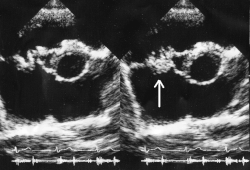

![]() Вегетации митрального клапана при инфекционном эндокардите. | |

Важное условие развития ИЭ — повреждение эндокарда или эндотелия, которое может возникать в результате пороков клапанов, микротравм, операции, проникновения инородных тел и др. К повреждённому эндотелию прикрепляются тромбоциты, образуется небольшой, первоначально стерильный тромб. Затем такой тромб инфицируется различными возбудителями, циркулирующими в крови. Таким образом формируется вегетация, состоящая из бактерий, фибрина, лейкоцитов и тканевого детрита. Вегетация — характерный признак ИЭ, обнаруживаемый при Эхокардиоскопии. Сами бактерии также способны напрямую повреждать клапаны сердца с образованием различных дефектов, фистул и абсцессов.